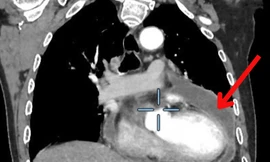

TPO - Nữ bệnh nhân nhập viện trong tình trạng bị đau ngực kéo dài không rõ nguyên nhân. Qua chẩn đoán hình ảnh, bác sĩ phát hiện bệnh nhân bị lóc thành động mạch, nguy cơ đột tử bất kỳ lúc nào.